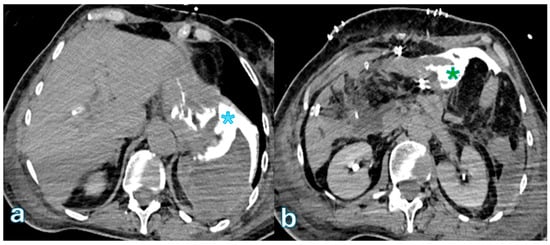

3. Biliary Leakage

The International Study Group of Liver Surgery (ISGLS) defines biliary leakage after pancreaticoduodenectomy as a drain fluid bilirubin concentration that is at least three times higher than plasma bilirubin levels, measured on or after the third postoperative day [96,97]. This condition can occur in as many as 8% of cases [16,20,98]. Although biliary fistulas are less frequent than postoperative pancreatic fistulas and are linked to a reduced risk of complications and death, they can nevertheless result in secondary complications, especially the formation of an intra-abdominal abscess, which may call for further treatments [21,41,99,100]. The primary risk factors for biliary leakage include excessive dissection of the hepatic duct (“skeletonization”), which can compromise vascular supply and healing; a small bile duct diameter, which increases anastomotic tension and impairs healing potential; and anastomosis involving the common bile duct, which presents technical challenges in maintaining an adequate seal [62,101,102,103]. To minimize these risks, several protective strategies have been developed, including refined reconstruction techniques to enhance anastomotic integrity, percutaneous biliary drainage to divert bile and promote fistula closure, and intraoperative T-tube placement to provide controlled bile drainage and reduce anastomotic stress [29,104,105,106,107]. In cases of biliary leakage, fluid collections are typically observed near the choledochojejunostomy, requiring cross-sectional imaging for accurate assessment [108,109,110]. On contrast-enhanced computed tomography (CECT), biliary leakage appears as homogeneously hypoattenuating fluid collections, generally without a well-defined capsule [4,46,111,112] (Figure 1).

On MRI, T1-weighted imaging (T1WI) demonstrates hypointense collections, while T2-weighted imaging (T2WI) shows hyperintense fluid accumulations, consistent with bile extravasation [113,114]. One of the main diagnostic challenges in imaging biliary leakage is differentiating it from a pancreatic fistula, given the close anatomical relationship between the choledochojejunostomy and pancreaticojejunostomy. Since both complications can present with fluid collections in similar locations, clinical correlation and biliary-specific imaging techniques are crucial for accurate diagnosis. Magnetic resonance cholangiopancreatography (MRCP) with HBAs can help in distinguishing these conditions [115,116]. By administering HBAs and acquiring images during the hepatobiliary phase (HBP), it is possible to directly visualize active bile leakage, as the contrast extravasates into the fluid collection, confirming a biliary origin HBA [117]. Since HBAs do not fill the pancreatic duct, the absence of contrast in the pancreatic region further differentiates it from a pancreatic fistula [48,118]. Studies have demonstrated that HBP-enhanced MRI using Gd-EOB-DTPA, when combined with MRCP, significantly improves diagnostic accuracy in detecting biliary leaks [119,120]. Compared to MRCP alone, this combined approach has shown an accuracy of 84%, a specificity of 100%, and a statistically significant improvement (p < 0.05) in diagnostic performance [121,122,123]. These findings emphasize the importance of HBP-enhanced MRI in optimizing the detection and characterization of biliary leaks, thereby improving the management of postoperative complications.